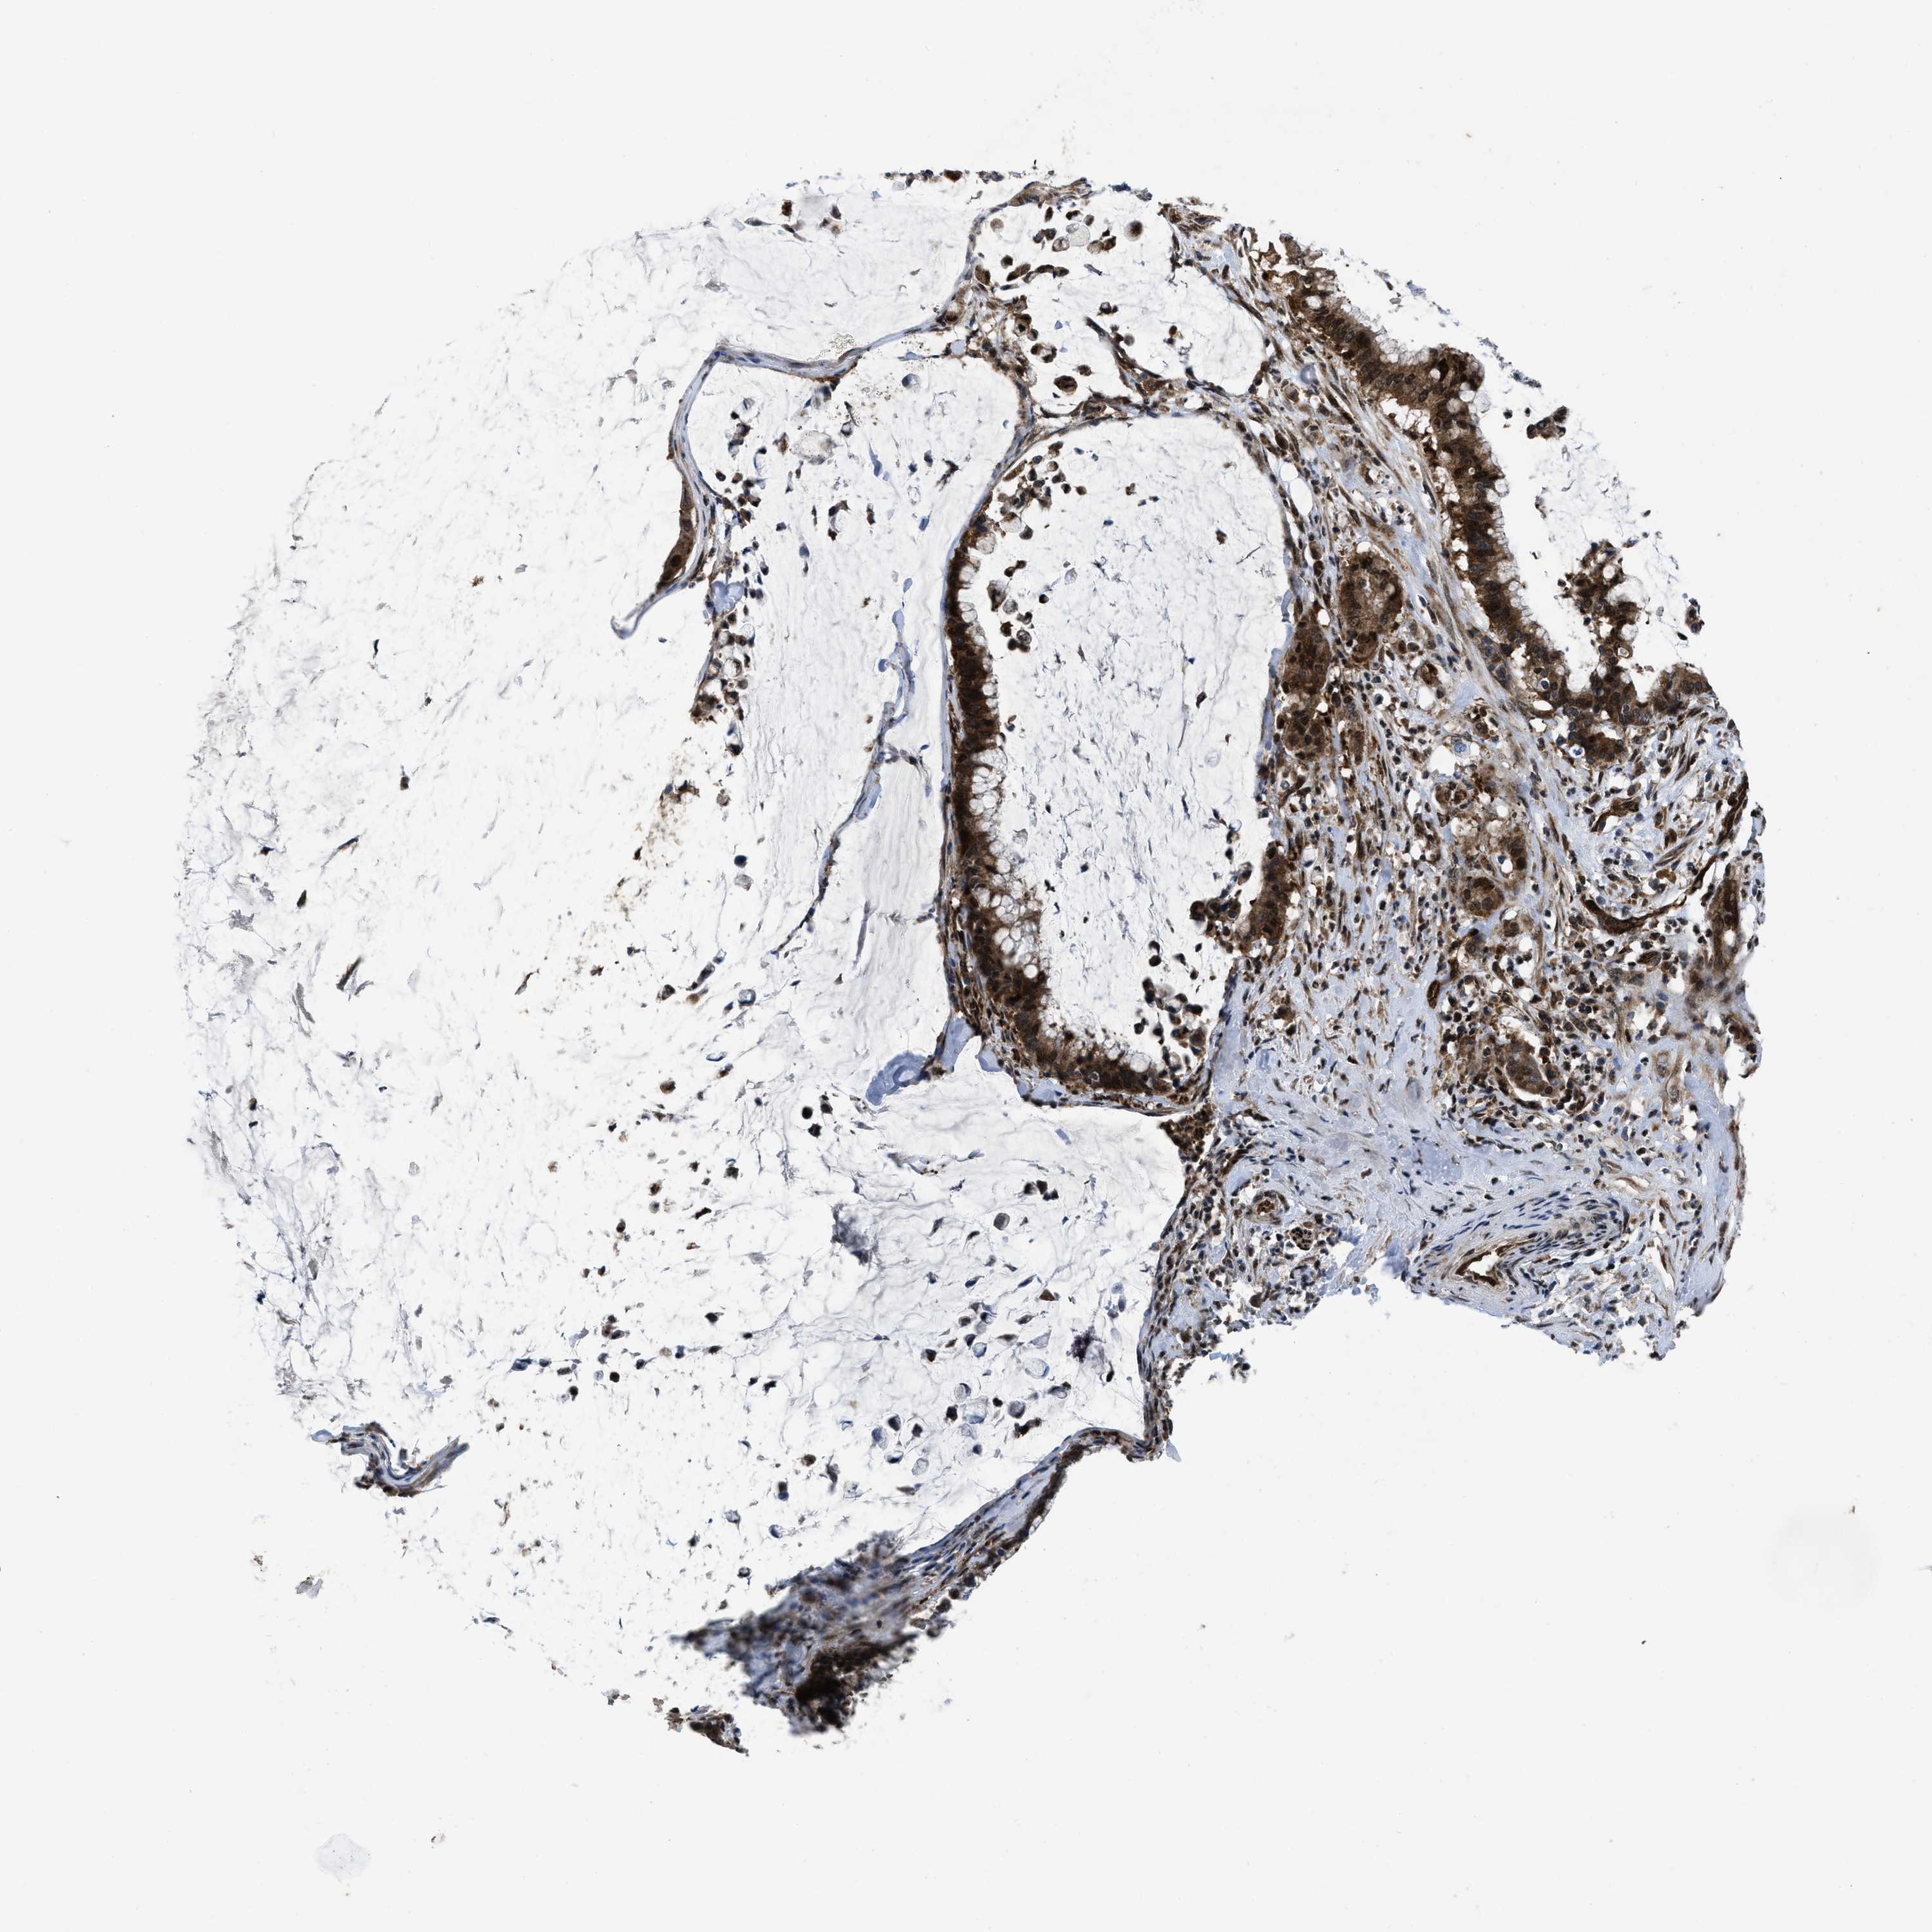

PANCREATIC CANCER - Protein expressioni

A mouse-over function shows sample information and annotation data. Click on an image to view it in a full screen mode. Samples can be filtered based on level of antibody staining by selecting one or several of the following categories: high, medium, low and not detected. The assay and annotation is described here.

Note that samples used for immunohistochemistry by the Human Protein Atlas do not correspond to samples in the TCGA dataset.

Antibody stainingi

Antibody staining in the annotated cell types in the current human tissue is reported as not detected, low, medium, or high, based on conventional immunohistochemistry profiling in selected tissues. This score is based on the combination of the staining intensity and fraction of stained cells.

Each image is clickable and will lead to virtual microscopy that enables deeper exploration of all samples and also displays staining intensity scores, fraction scores and subcellular localization as well as patient and tissue information for each sample.

Antibody HPA043236

Antibody CAB018600

Staining

High

Medium

Low

Not detected

Intensity

Strong

Moderate

Weak

Negative

Quantity

>75%

75%-25%

<25%

None

Location

Nuclear

Cytoplasmic/membranous

Cytoplasmic/membranous,nuclear

Adenocarcinoma, NOS